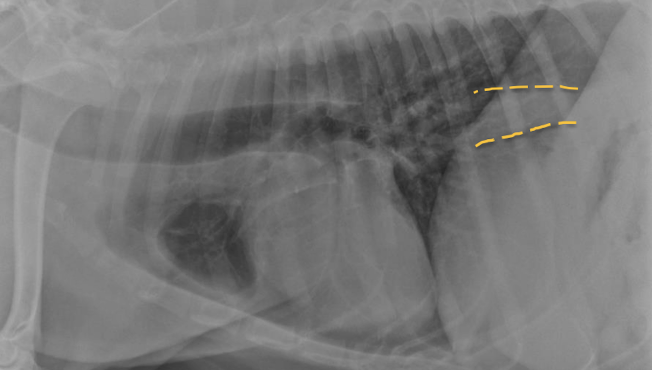

11

Esophageal dilation

Arrow = tracheal stripe